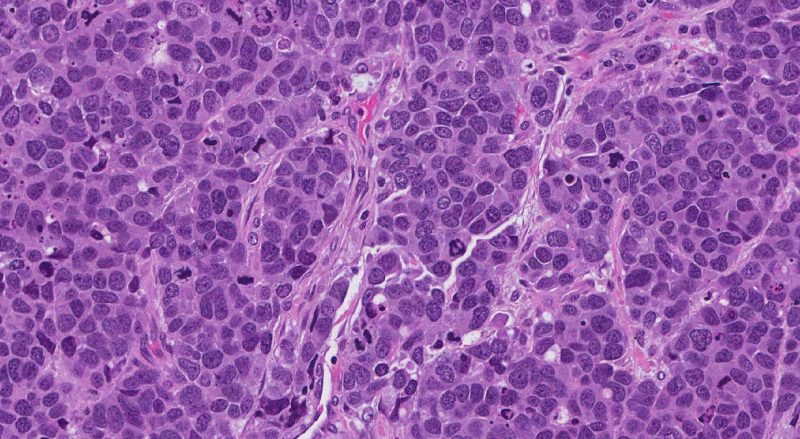

Die Dissonanz des Genoms mit dem Wellenfeld verursacht eine Verschiebung des Chromatins relativ zu den aktiven Zonen, was zu einer Verletzung der Aktivierungsaktivierung führt, mit einem raschen Übergang zu einer chaotischen Zunahme der Anzahl der transkribierten Gene. Diese Situation ist das charakteristischste Merkmal fast jeder Krebsentstehung. Es kann argumentiert werden, dass in all diesen Fällen die normale Anordnung von Genen im Raum des Kerns gestört ist.

Dies legt nahe, dass alle menschlichen Tumorzellen ausnahmslos unterschiedliche Chromosomenanomalien aufweisen (einschließlich Translokationen, Deletionen und Duplikationen).

Sehr oft geht die Karzinogenese mit schwerwiegenden Verzerrungen der Kernmembran oder Deformationen des Kerns einher, beispielsweise unter dem Druck von Hormonen, die das Zellgranulat überwältigen. Offensichtlich gibt es Verzerrungen in Form eines Kerns mit einer ihm nicht eigenen Kontur, eine Invagination oder das Vorhandensein von Fremdformationen in der Zelle, die verhindern, dass der Kern die gewünschte Form oder Position frei annimmt.

Der Hauptunterschied zwischen den Zellen von bösartigen Tumoren liegt in der Störung der normalen Koordination der Gene innerhalb der Kerne, in der Verzerrung der eigentlichen Konfiguration des Genoms, und die Antikörper reagieren überhaupt nicht auf solche Unterschiede.